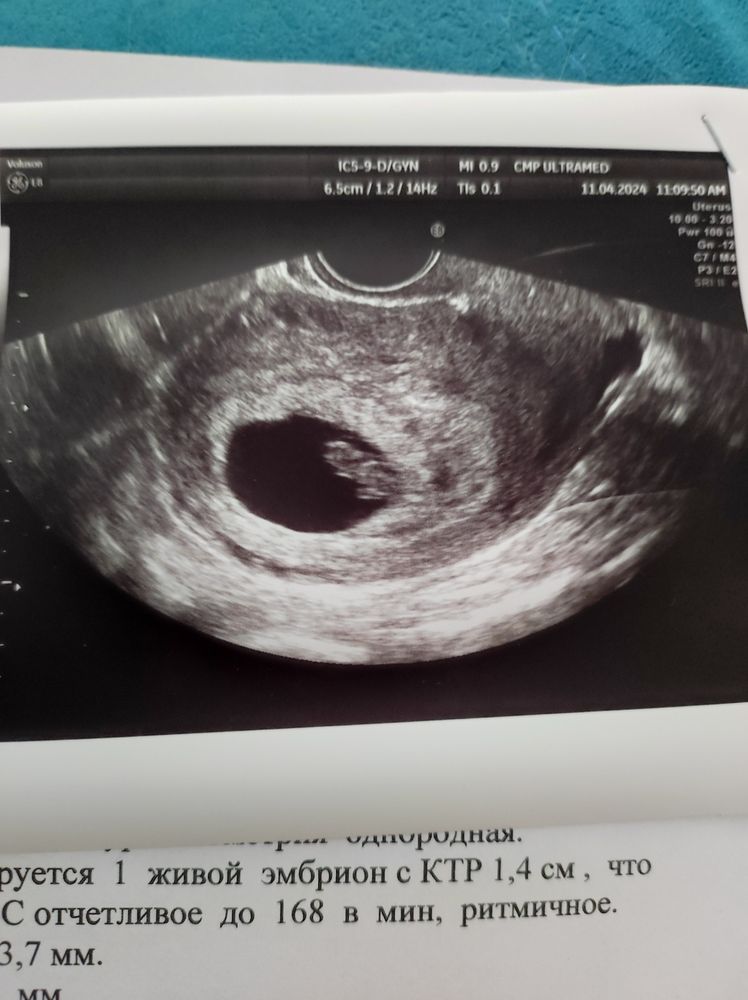

Второе УЗИ на сроке 7 и 6 (по месячным)

Срок по КД сейчас 7 и 6, по УЗИ 7 и 5 (Hadlock).

КТР 1,4 см

ЧСС 168

ЖМ 3,7 мм